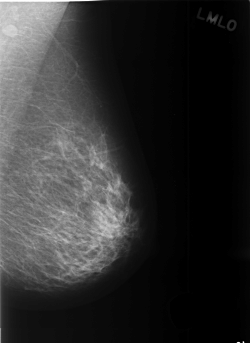

C_0374_1.LEFT_MLO

LEFT_MLO LINES 5480 PIXELS_PER_LINE 4000 BITS_PER_PIXEL 12 RESOLUTION 50 NON_OVERLAY